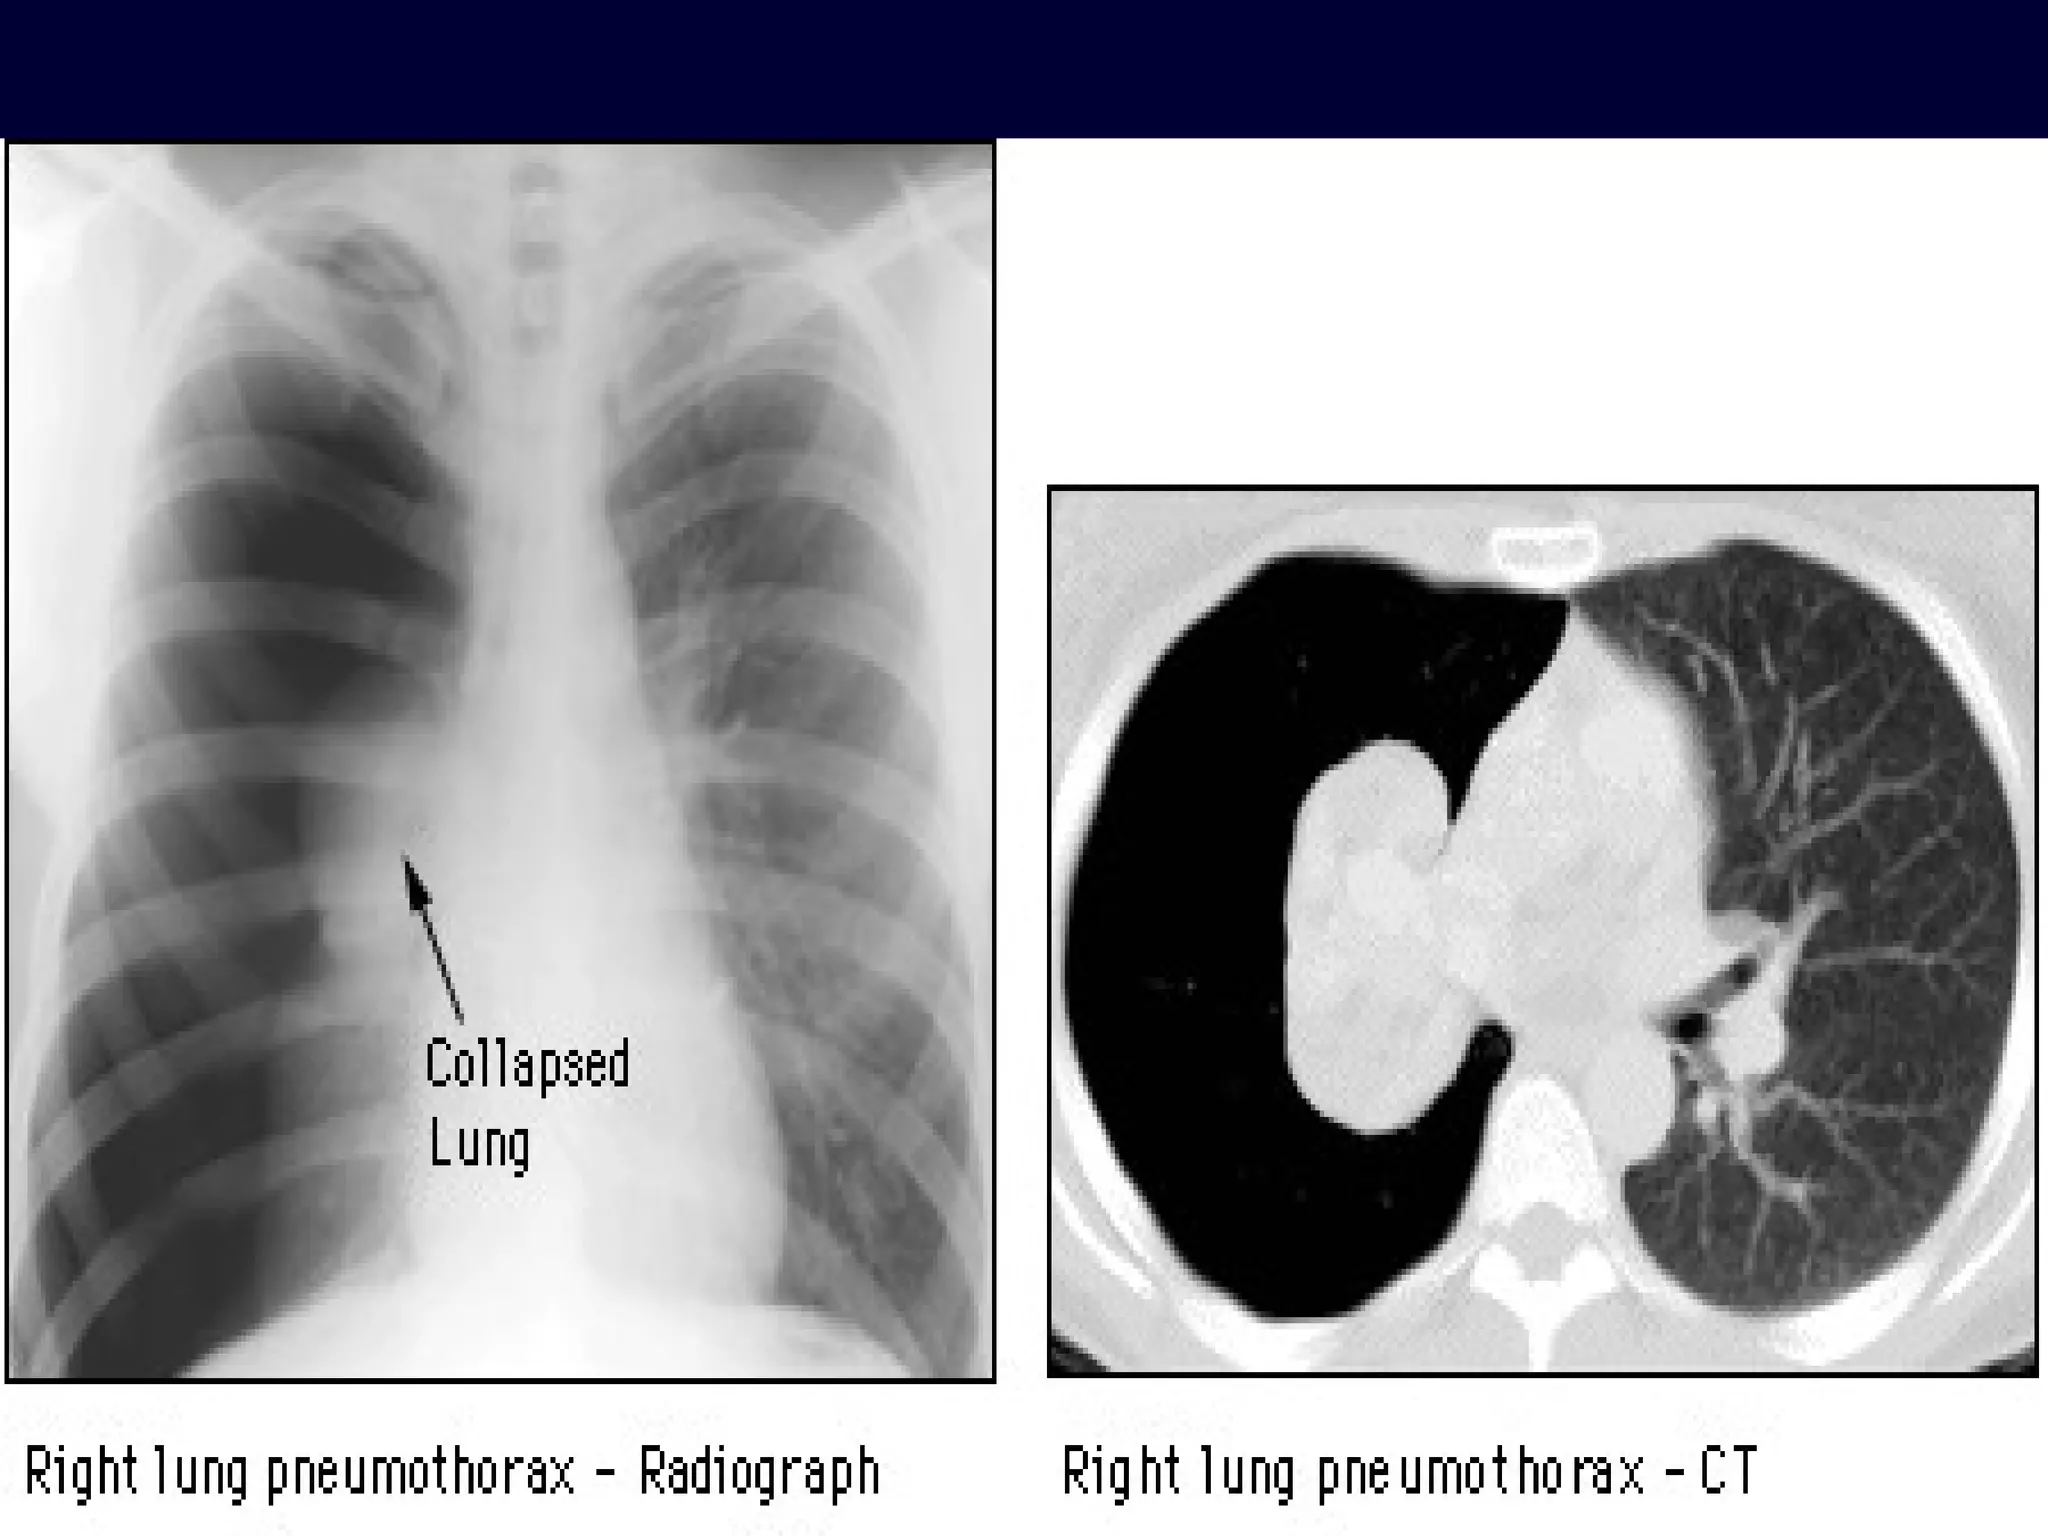

Imaging- Plane chest X-ray film  Establishing the diagnosis The characteristics of pneumothorax Pleural line No lung markings in pneumothorax The outer margin of visceral pleura separated from the parietal pleura by a lucent gas space devoid of pulmonary vessels

Plane chest X-ray film In erect patients, pleural gas collects over the apex, and the space between the lung and chest wall is most notable there In the supine position, gas migrates along the broad ventral surface of lung, making detection on a frontal radiograph difficult

Imaging- Plane chestX-ray film Establishing the diagnosis The characteristics of pneumothorax Pleural line No lung markings in pneumothorax The outer margin of visceral pleura separated from the parietal pleura by a lucent gas space devoid of pulmonary vessels

Plane chest X-rayfilm In erect patients, pleural gas collects over the apex, and the space between the lung and chest wall is most notable there In the supine position, gas migrates along the broad ventral surface of lung, making detection on a frontal radiograph difficult